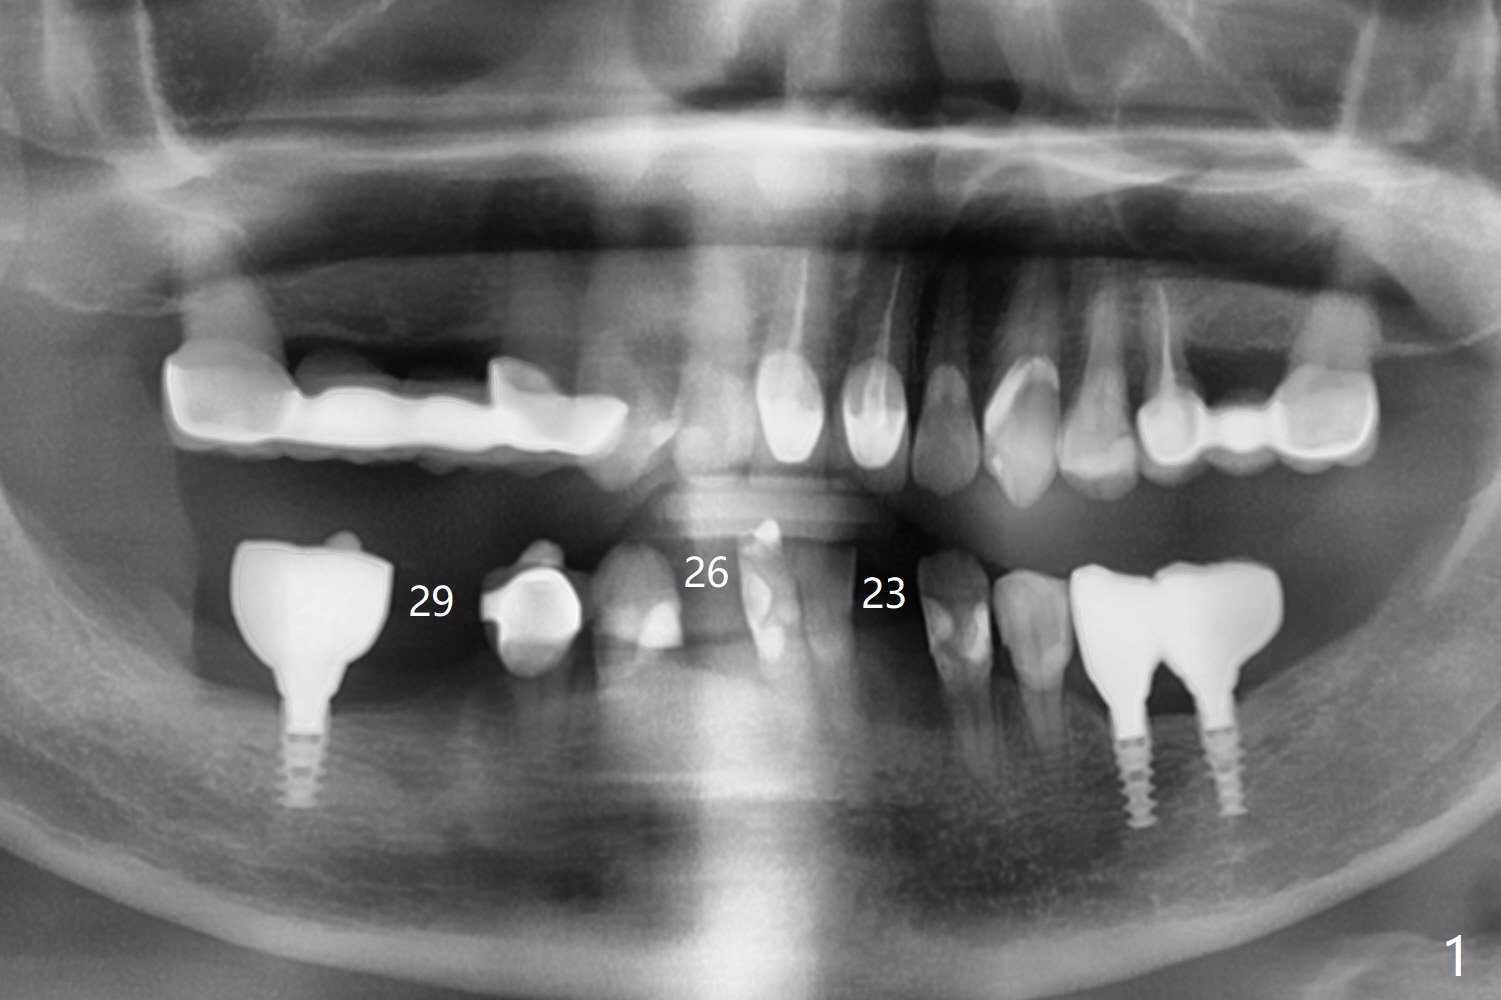

57岁女,口干症,前一个月(23,29号牙),三个月(26号牙)拔除植骨,可能需要再等一个月(出差)才能手术,会不会太早植牙?骨质还不够

植骨后2-3个月会不会太早植牙?